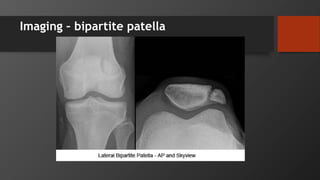

Imaging

Imaging – bipartite patella